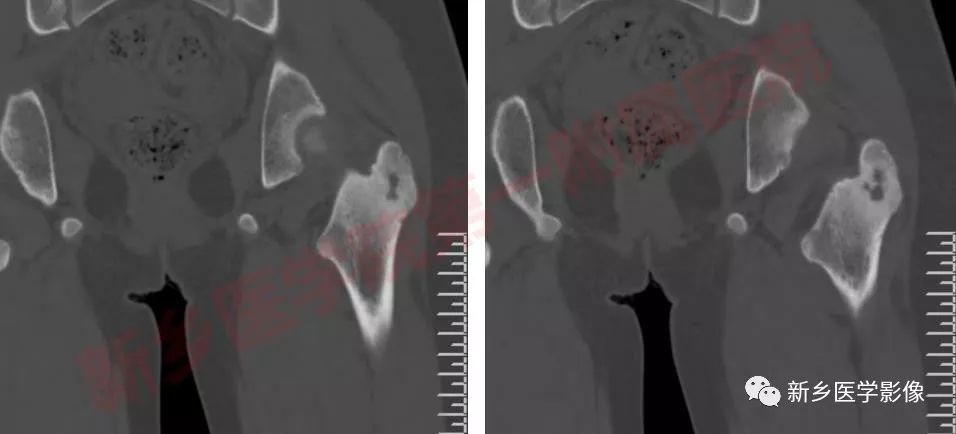

影像表现:

骨样骨瘤的影像学表现具有特征性,其典型的表现为:

瘤巢所在部位的骨质破坏及周围不同程度的骨质硬化,还可伴有骨膜反应、周围软组织或相邻关节的肿胀。

松质型:最常见于股骨颈,其次是手足的小骨和椎体,瘤巢位于骨端或不规则骨,周围硬化不明显,可仅有骨硬化边,病灶周围常无 新骨形成,但有密度增加的骨环包绕病灶。

骨膜下型:瘤巢位于骨皮质表面或骨膜下,肿瘤可侵蚀骨皮质形成浅凹状缺损,其表面形成数量不等的骨膜新生骨,通常骨附近的软组织肿块,最常见于股骨颈的内面及手和足。

—CT/平片:低密度,但内部的骨组织表现高密度

CT/平片上,“瘤巢”周围多出现反应性骨质增生硬化:松质骨增生硬化或骨膜反应